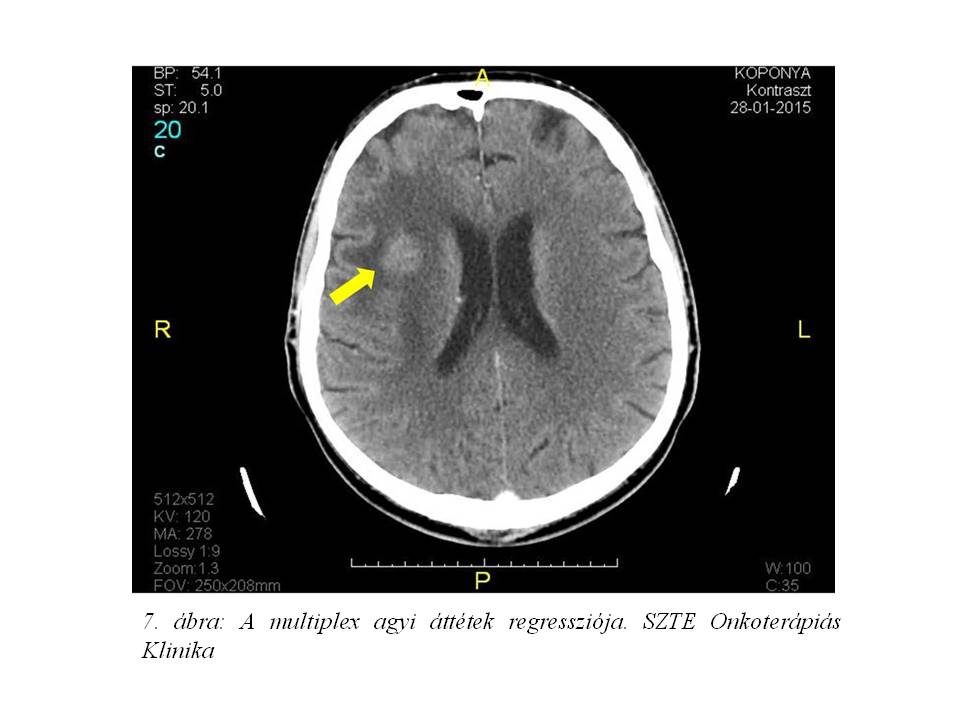

A kezelés megkezdése előtt kontroll koponya CT vizsgálat készült, mely a korábbi multiplex gócoknál regressziót véleményezett (7. ábra, 8. ábra).